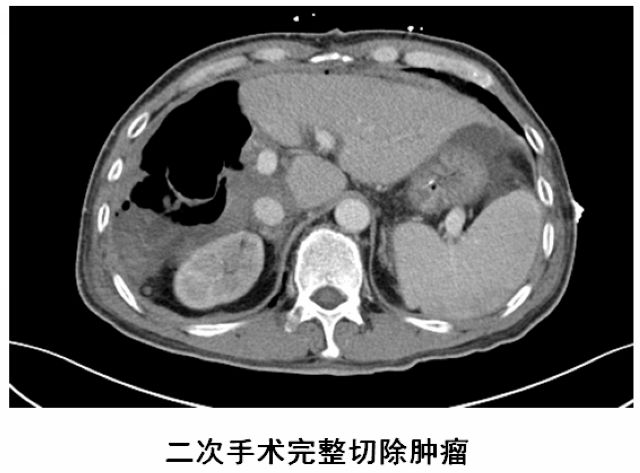

经过20天左右的“养肝”,经CT复查显示,患者的左侧肝脏体积已增长至42.8%,这时候,也就达到了我们说的“养大好肝、再切病肝”,因为此时好肝已经足以维持患者身体的运转需要。

于是,专家团队便于10月中旬为患者实施了第二阶段肿瘤切除术,在此过程中,由于患者同时合并腹茧症,通过第一次手术的刺激腹腔内粘连非常严重,手术遭遇了巨大的困难,最后经过近7小时左右的艰苦奋战,攻坚克难,终于完整切除了患者右肝的巨大肿瘤,手术取得了成功,患者重获新生。